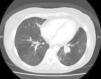

Paciente exfumadora de 38años, diagnosticada de leucemia aguda, que fue tratada con quimioterapia, radioterapia y posteriormente con un trasplante alogénico de médula ósea de donante no emparentado HLA idéntico, tras el cual sufrió enfermedad de injerto contra huésped cutánea y pulmonar, así como infecciones respiratorias de repetición. Ingresó por hemoptisis de unos 50cc, sin referir clínica infecciosa. Presentaba mínima leucocitosis, hipoxemia leve y un aumento de densidad en el lóbulo inferior izquierdo. En la TC de tórax se objetivó una ocupación de bronquios segmentarios en la base pulmonar izquierda (fig. 1). La broncoscopia mostró una masa endobronquial con placas blanquecinas, muy vascularizada, tomándose biopsias que no evidenciaron malignidad. Tras resección endobronquial por láser, se informó como adenocarcinoma con áreas mucinosas, compatible con origen pulmonar, con estudio inmunohistoquímico positivo para citoqueratina7 (CK7) y antígeno carcinoembrionario. Se realizó una lobectomía inferior izquierda mediante videotoracoscopia, con linfadenectomía mediastínica. Se identificó una lesión endobronquial polipoide parda de 3cm, revestida de epitelio bronquial conservado y con afectación de la pared bronquial, sin sobrepasarla. No infiltraba el paquete vascular ni el parénquima pulmonar. El patrón de crecimiento era glandular, con abundante material mucoide. No se objetivó mitosis, pleomorfismo nuclear ni necrosis. La celularidad neoplásica era CK7 positiva, con factor de transcripción tiroideo-1 y cromogranina negativos, mostrando positividad aislada para p63. Diagnóstico definitivo: carcinoma mucoepidermoide endobronquial de bajo grado, con borde quirúrgico libre y ganglios hiliares sin afectación neoplásica. La paciente sigue revisiones periódicas y hasta la fecha no se ha detectado recidiva tumoral.